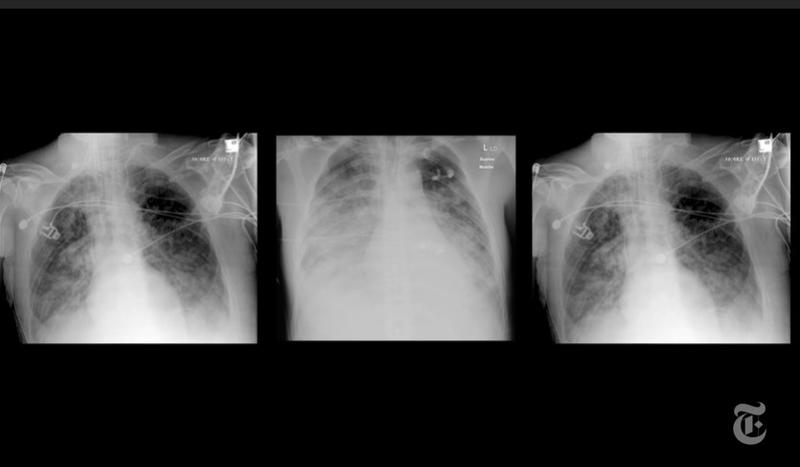

Potrivit acestora, timp de șase săptămâni după ce au părăsit spitalul, 88% dintre pacienți prezentau încă leziuni, vizibile la ecografie, cum ar fi aspectul de cioburi de sticlă în plămâni. În același timp, 47% aveau probleme de respirație.

La 12 săptămâni distanță de momentul externării, procentele pentru cele două categorii erau de 56% și, respectiv, 39%.